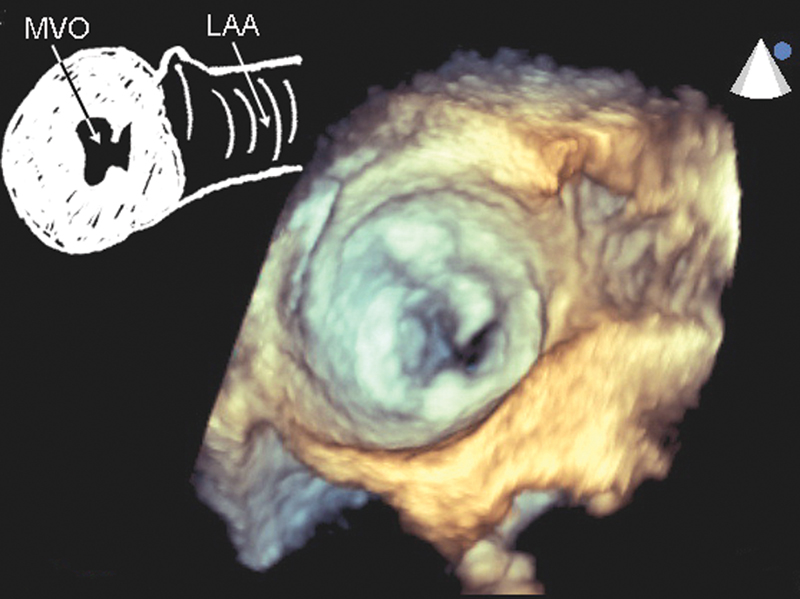

فحوصات تشخيصية لبعض امراض القلب والشرايين التاجية